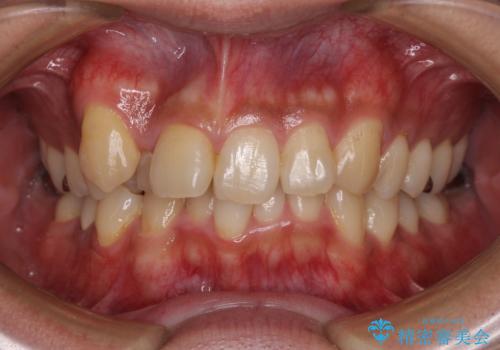

【モニター】八重歯と正中のずれた歯列 片顎抜歯のワイヤー矯正